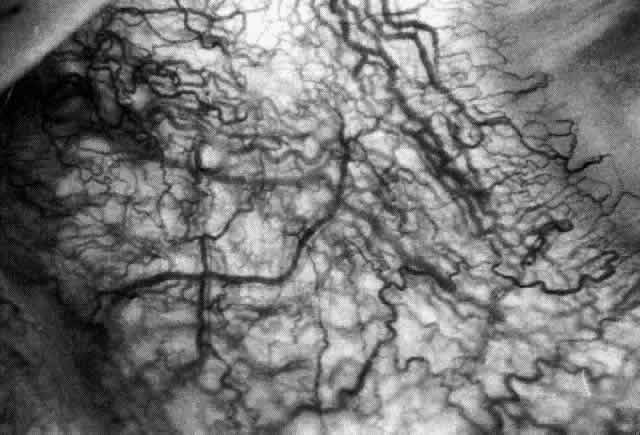

With the increasing use of anterior segment fluorescein angiography in the early detection of severe necrotizing disease of the sclera, it is necessary to have an understanding of the normal anatomy of the vasculature of the anterior segment of the eye.3–5 The blood supply to this region is enormous, being derived from the anterior ciliary arteries, but with extensive collateral arterial anastomoses to the posterior ciliary arteries at the root of the iris (Fig. 1). The anterior system is readily visible with the slit lamp and by anterior segment fluorescein angiography, especially if the eye is inflamed, and its recognition is of vital importance in the differentiation of episcleral and scleral conditions. The separation and displacement of these vascular layers give the most important clinical clues to the site and, hence, the severity of the inflammation. On slit lamp examination, three layers of vessels are readily visible. The conjunctival plexus, which is the most superficial layer of vessels, can be moved over the underlying structures. The superficial episcleral capillary plexus (Fig. 2) is a radially arranged series of vessels lying within the parietal layer of Tenon's capsule. The vessels in this layer anastomose at the limbus with the conjunctival vessels, with other members of the same plexus, and with the deep plexus. The deep episcleral capillary network (see Fig. 2) is closely applied to the sclera in the visceral layer of Tenon's capsule. The vessels anastomose freely with each other, forming a syncytium. The large vessels to and from the intrascleral plexus traverse the episclera near the insertions of the muscles. The conjunctival and superficial episcleral vessels can be blanched with 1:1000 epinephrine or 10% phenylephrine, but the deep vessels are affected slightly. This is of considerable assistance when attempting to differentiate deep and superficial inflammation.

Fig. 1. Anterior view montage of a cynomolgus monkey ocular casting with Tenon's and episcleral vessels removed. The anterior ciliary arteries (ACA) arborize at the limbus and interconnect via their lateral branches to form the episcleral circle. (CM, ciliary muscle capillary bed; CV, choroidal veins; EC, episcleral circle. (Original magnification, X20). (Morrison JC, van Buskirk EM: Anterior collateral circulation in the primate eye. Ophthalmology 90:707, 1983)

Fig. 2. The normal relationships of the capillary networks that can be seen with the slit lamp are a conjunctival (easily mobile) network, a superficial episcleral network in the parietal layer of Tenon's capsule, and a deep episcleral plexus closely applied to the sclera. These relationships are much more obvious in inflamed eyes (see Figs. 13, 14, and 30). (Watson PG, Hayreh S, Awdry P: Episcleritis and scleritis. Br J Ophthalmol 52(3):278– 279, 1968)